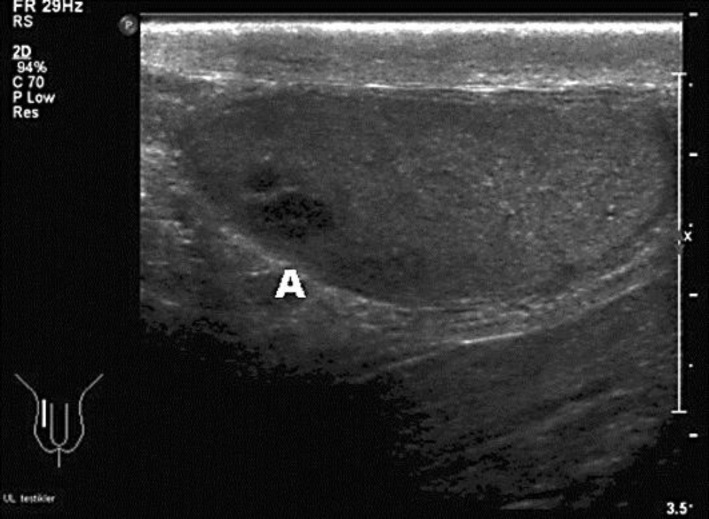

Hemospermia is often considered idiopathic. We report a case of a patient who presented with hemospermia. Scrotal examination and ultrasonography found a testis tumor. This case underscores the importance of scrotal examination and eventually ultrasound in patients presenting with hemospermia.

血精症通常被认为是特发性的。我们报告一例患者谁提出了血精症。阴囊检查及超声检查发现睾丸肿瘤。本病例强调了阴囊检查的重要性,并最终超声对患者提出了血精。